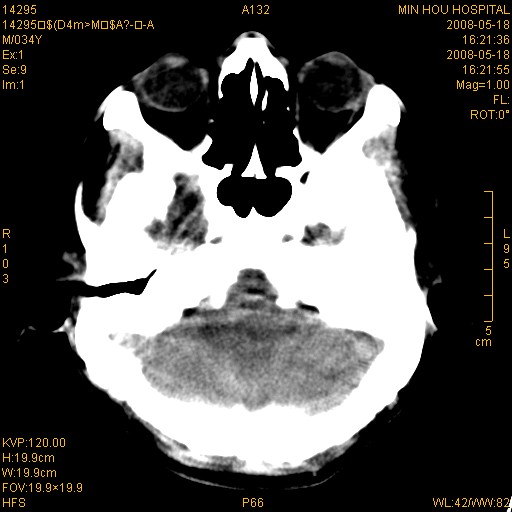

标题: CT13617:双顶叶白质水肿伴大脑镰小脑幕广泛钙化 [打印本页]

标题: CT13617:双顶叶白质水肿伴大脑镰小脑幕广泛钙化

多年前频发抽搐生活不能自理,行ct平扫,诊断为双顶叶占位。因贫未能进一步检查。

目前偶有抽搐,能从事油漆工作。原片未能获取。

双侧侧脑室后脚旁对称性低密度影,符合肾上腺白质营养不良(成人型)改变    小脑幕及大脑廉钙化  可考虑为生理性

支持:1、肾上腺白质营养不良.2、小脑幕、大脑镰广泛钙化。3、建议进一步检查。

硬脑膜钙化是主因,双侧顶叶白质密度减低是可能由于静脉路回流受阻所致。